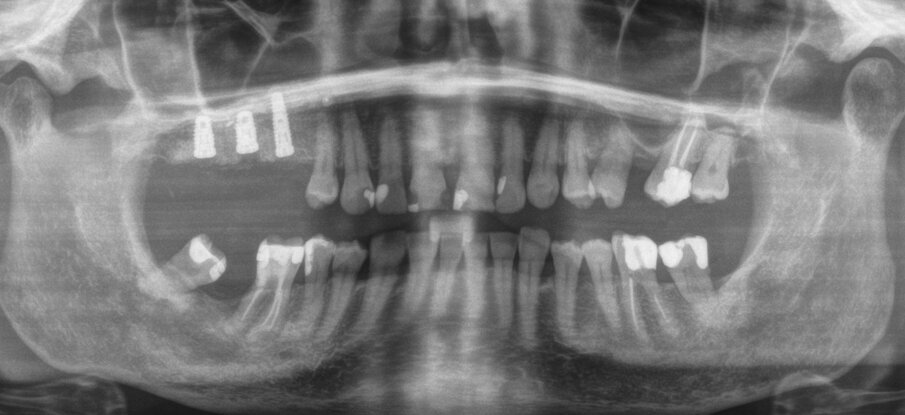

Una paziente di 62 anni, ASA I, non fumatrice e non diabetica, con malattia parodontale precedentemente trattata, si è presentata per una riabilitazione implanto-protesica del mascellare superiore (Fig. 1). L’analisi radiografica, eseguita tramite ortopantomografia (OPT) e tomografia computerizzata cone-beam (CBCT), ha rilevato la presenza di un difetto osseo verticale nel primo sestante, dovuto alla completa perdita del processo alveolare (Figg. 2, 3). Dopo aver discusso con la paziente le possibilità di trattamento, è stato accettato il trattamento proposto come prima scelta, ovvero la ricostruzione ossea del processo alveolare e la successiva riabilitazione mediante corone singole su impianti.

Dopo 14 giorni, sono state rimosse le suture, sono stati raccolti dati relativi al decorso post-operatorio, è stata verificata l’assenza di deiscenze o esposizione o infezione della griglia, ed è stata eseguita una radiografia OPT (Fig. 22). La paziente ha riferito un livello medio di dolore pari a 0, su una scala VAS da 0 a 10, con una media di 1,6 FANS assunti al giorno, durante le prime 2 settimane; inoltre, la paziente ha riferito gonfiore significativo, un piccolo livido esterno sul volto, e la difficoltà ad aprire la bocca. Secondo il questionario Postoperative Symptom Severity (POSSe), si è registrato un valore di 32, indicativo di un moderato disagio postoperatorio.